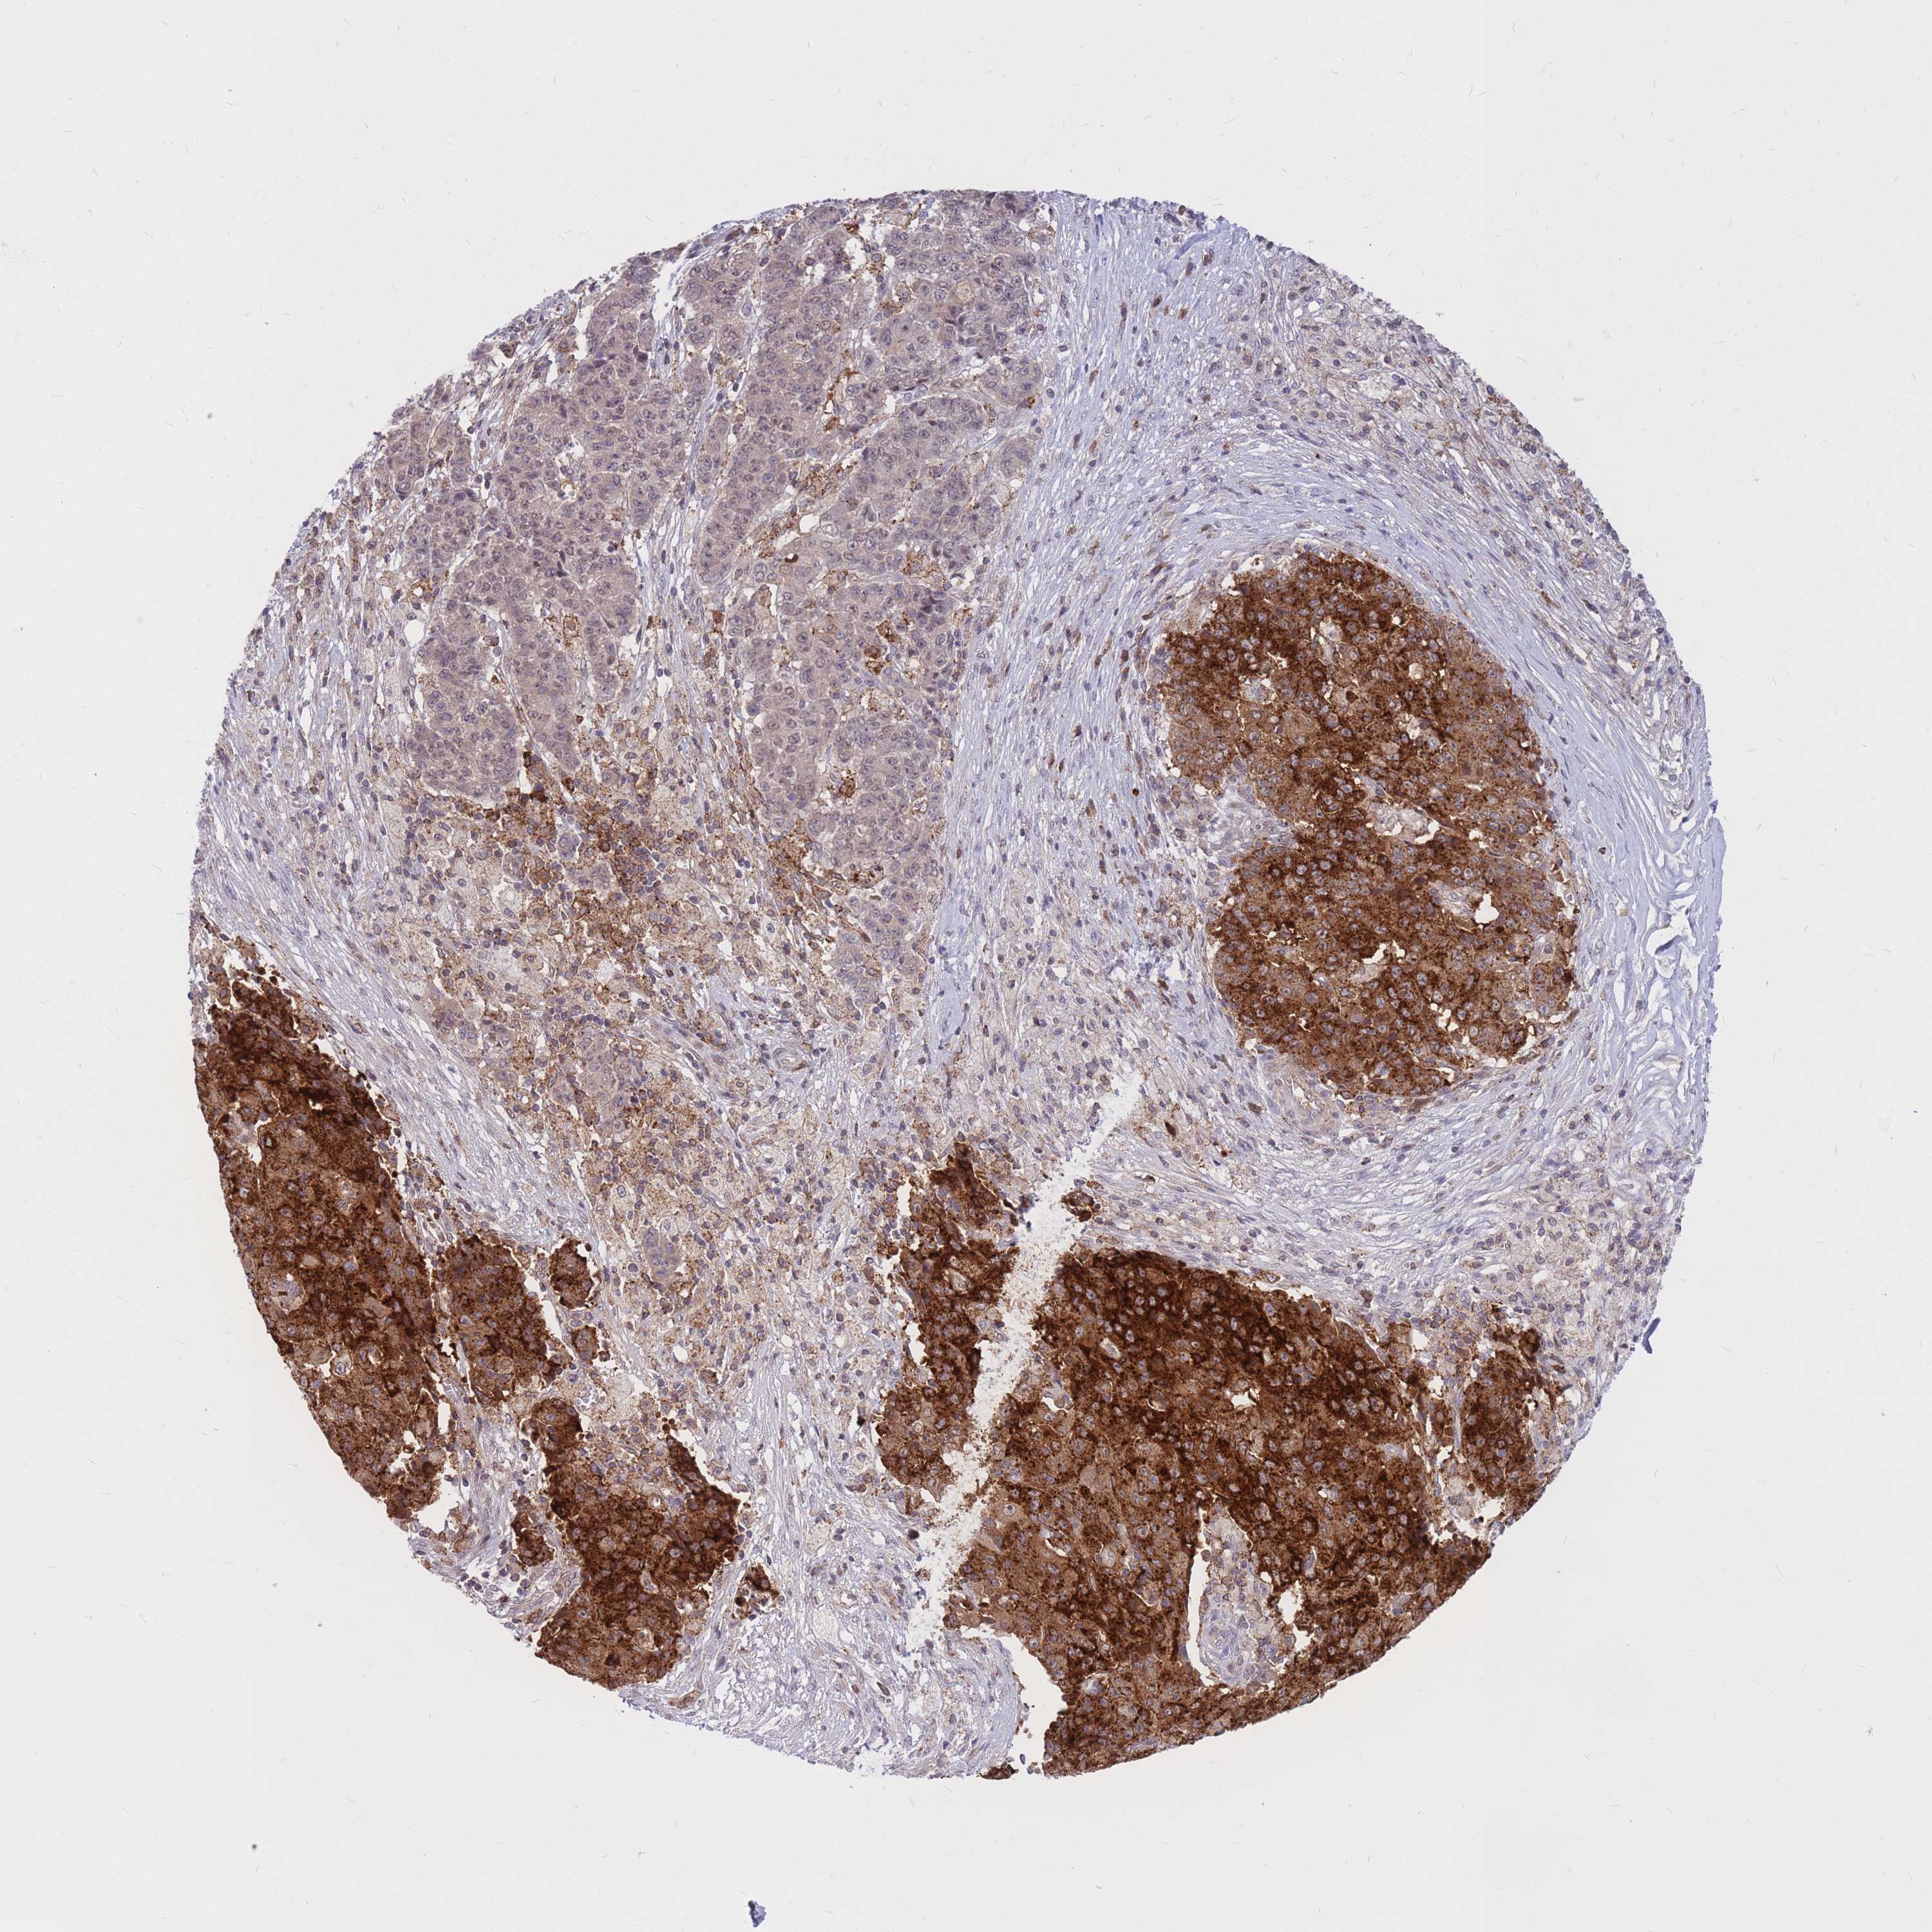

OVARIAN CANCER - Protein expressioni

A mouse-over function shows sample information and annotation data. Click on an image to view it in a full screen mode. Samples can be filtered based on level of antibody staining by selecting one or several of the following categories: high, medium, low and not detected. The assay and annotation is described here.

Note that samples used for immunohistochemistry by the Human Protein Atlas do not correspond to samples in the TCGA dataset.

Antibody stainingi

Antibody staining in the annotated cell types in the current human tissue is reported as not detected, low, medium, or high, based on conventional immunohistochemistry profiling in selected tissues. This score is based on the combination of the staining intensity and fraction of stained cells.

Each image is clickable and will lead to virtual microscopy that enables deeper exploration of all samples and also displays staining intensity scores, fraction scores and subcellular localization as well as patient and tissue information for each sample.

Antibody HPA036786

Antibody CAB017849

Cystadenocarcinoma, serous, NOS